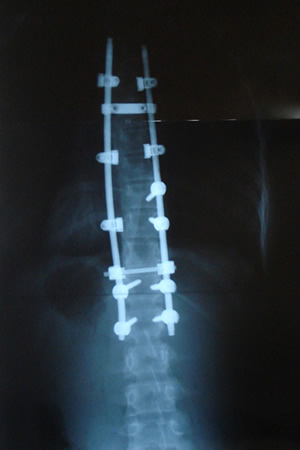

Grafilerle Skolyoz